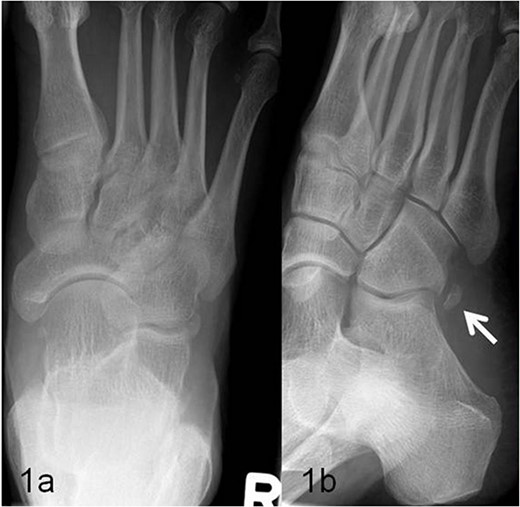

A 59-year-old man reported severe, load-dependent pain (7 out of 10 score points on the VAS) of his right foot, increasing over a period of about 1 month. He had no memory of having experienced trauma. Clinically, there was a pes planovalgus, a slight swelling, and warm sensation distolaterally of the malleolus lateralis over the course of the tendon of the peroneus longus muscle, where there was also clear pain upon pressure, and forced plantar flexion was very painful. For imaging diagnostics, conventional X-rays were taken, which revealed an elongated oval os peroneum with a size of 9.5 × 5 mm in a typical location (Fig. 1a and b). Furthermore, an MRI examination was performed, which revealed a clear perifocal soft tissue oedema of the os peroneum with involvement of the peroneus longus muscle, whereas a tendon rupture was ruled out (Fig. 2a and b).

(a, b) Presentation of the os peroneum (marked with an arrow) in the oblique X-ray image.

In addition to conventional X-rays, ultrasound and MRI are used for differential diagnosis and treatment planning. A dislocation, fracture, hypertrophic, or multisegmental form of the peroneal bone, with or without accompanying perifocal irritation and tenosynovitis or rupture of the long peroneal tendon, can be visualized effectively [7–13]. In our patient, an os peroneum of normal size and localization was found on conventional X-ray (Fig. 1a and b). In the MRI examination, there was clear perifocal soft tissue oedema with a tenosynovitis of the tendon of the peroneus longus muscle (Fig. 2a and b). At the same time, the arch of the foot was lowered and there was a marked pes planovalgus, so that, when everything was taken into consideration, it was assumed that our patient had subacute/chronic postural stress with accompanying perifocal inflammation.